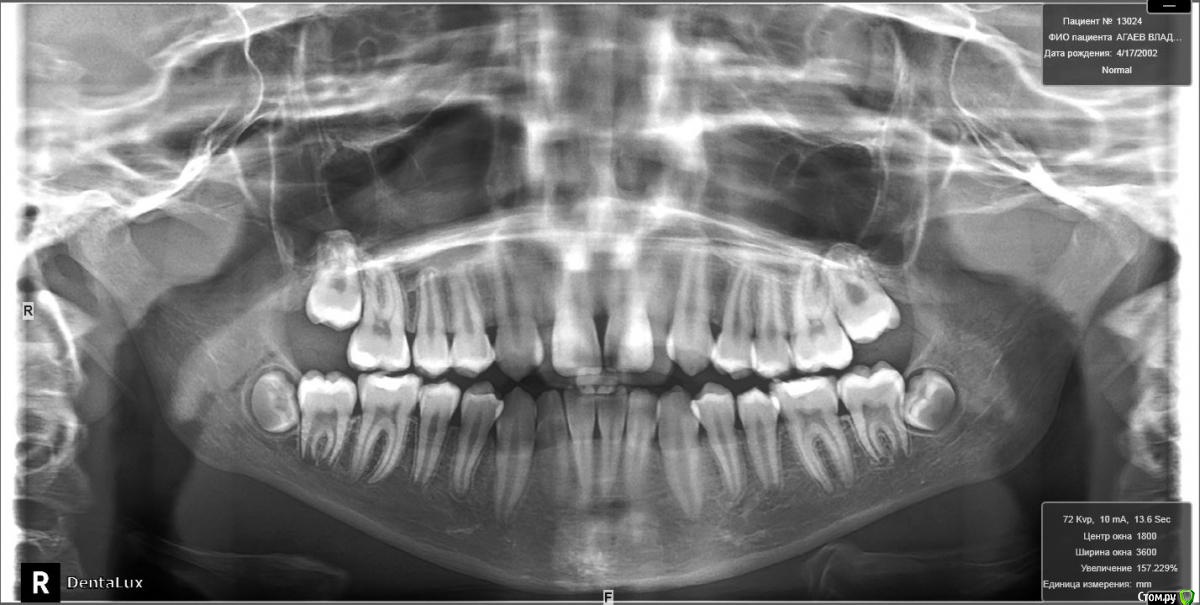

Yana guapa Опубликовано 26 августа, 2015 Поделиться Опубликовано 26 августа, 2015 как только прорежутся нижние 7-ки, я бы сразу послала бы на удаление зачатков нижних 8-ок. аппарат RPE конечно можно поставить. но 13 лет - критический возраст. стоит вопрос о необходимости SARPE. иначе можем получить результат только на уровне зубов (просто их наклонт будет). а Если хотим реально челюсть расширить, то лучше вместе с хирургом. И по срокам быстрее , и результативнее и стабильнее. 1 Ссылка на комментарий

Molox Опубликовано 27 августа, 2015 Поделиться Опубликовано 27 августа, 2015 Имхо, но раз апексы 5-к еще не сформировались, можно расчитывать на скелетный эффект. Ссылка на комментарий

Yana guapa Опубликовано 27 августа, 2015 Поделиться Опубликовано 27 августа, 2015 Имхо, но раз апексы 5-к еще не сформировались, можно расчитывать на скелетный эффект. не соглашусьапексы 5-ок не показатель. Если бы рентгенографию кисти предложили бы сделать и посмотреть зоны роста... это даст больше информации п.с. недавно была девочка у которой в 8,5 лет были уже 5-ки и наклевывались 7-ки!!!! ))) сейчас сроки прорезывания зубов и закрытие верхушек очень не постоянный параметр. Ссылка на комментарий

Molox Опубликовано 28 августа, 2015 Поделиться Опубликовано 28 августа, 2015 Тем более, что это мальчик. И в 14 лет можно твердо расчитывать на скелектный рост. Ссылка на комментарий

krokomot Опубликовано 28 августа, 2015 Поделиться Опубликовано 28 августа, 2015 14 лет замечательный возраст особенено для мальчиков срочно начинайте лечение Ссылка на комментарий

Maverick Опубликовано 29 августа, 2015 Поделиться Опубликовано 29 августа, 2015 Хайрекс вплоть до 15 лет дает хороший скелетный эффект. Никакого хирурга не надо. Зачем простое занятие превращать в травматичное, да и порой на которое родители не дают согласие. Мальчик такого возраста отличный пациент для скелетного расширения верхней челюсти. Как вариант посмотреть по позвонкам на трг на скелетный возраст , а судя по его трг, у него он еще есть. Так что вам ничего не мешает работать. Ссылка на комментарий